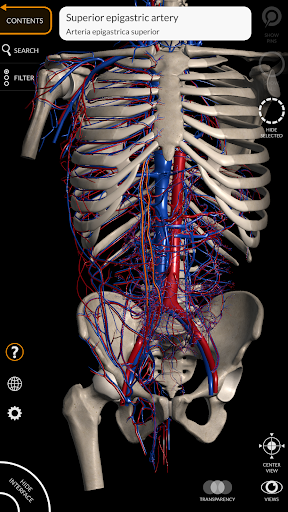

"Anatomía - Atlas 3D" permite estudiar la anatomía humana de forma fácil e interactiva.

A través de una interfaz sencilla e intuitiva es posible observar cada estructura anatómica desde cualquier ángulo.

Los modelos anatómicos 3D son especialmente detallados y con texturas de hasta una resolución de 4k.

• Sistema cardiovascular • Sistema

nervioso • Sistema respiratorio • Sistema digestivo • Sistema urogenital (masculino y femenino) • Sistema endocrino • Sistema linfático • Sistema ocular y auditivo CARACTERÍSTICAS • Interfaz sencilla e intuitiva • Rotar y hacer zoom en cada modelo en el espacio 3D • Opción para ocultar o aislar uno o varios modelos seleccionados • Filtro para ocultar o mostrar cada sistema • Función de búsqueda para encontrar fácilmente cada parte anatómica • Función de marcador para guardar vistas personalizadas • Rotación inteligente que mueve el centro de rotación automáticamente • Función de transparencia • Visualización de músculos a través de niveles de capas desde las superficiales hasta las más profundas • Al seleccionar un modelo o un pin, aparece el término anatómico relacionado • Descripción de los músculos: origen, inserción, inervación y acción • Mostrar/ocultar interfaz de usuario (muy útil con pantallas pequeñas) MULTILINGÜE • Los términos anatómicos y la interfaz de usuario están disponibles en 11 idiomas: latín, inglés, francés, alemán, italiano, portugués, turco, ruso, español, Chino, japonés y coreano • Los términos anatómicos se pueden mostrar en dos idiomas simultáneamente REQUISITOS DEL SISTEMA • Android 8.0 o posterior, dispositivos con al menos 3 GB de RAM Reversi

• Sistema cardiovascular